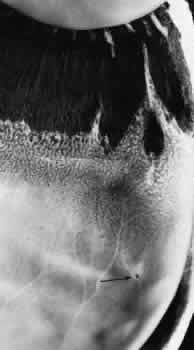

Enclosed and partially enclosed ora bays are relatively uncommon developmental variations. These are oval islands of pars plana epithelium located immediately posterior to the ora serrata and com-pletely or almost completely circumscribed by the peripheral retina (Figs. 11 and 12). The enclosed ora bay is composed of a thin layer of nonpigmented pars plana epithelium surrounded by neurosensory retina. Enclosed and partially enclosed ora bays are evident in 6% of patients, are bilateral in 8% of affected individuals, and are present in 3% of all eyes (see Table 2). These lesions are equally prevalent nasally and temporally near the horizontal meridian.6,7

Fig. 11. Partially enclosed ora bay in a 20-year-old woman. Posteriorly, the ora bay extends 1.8 mm behind general line of ora serrata, and the retina shows a large area of typical cystoid degeneration. Anteriorly, the ora bay is embraced by two long dentate processes that converge toward, but do not meet, a prominent ciliary process of the pars plicata. (× 12.)